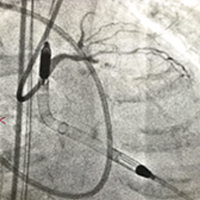

PCI8例、EVT5例、TAVI3例の手技をライブでお届けいたします。ハートセンター屈指のオペレーターをはじめ外部からもオペレーターをお招きし、様々な症例を用意しています。